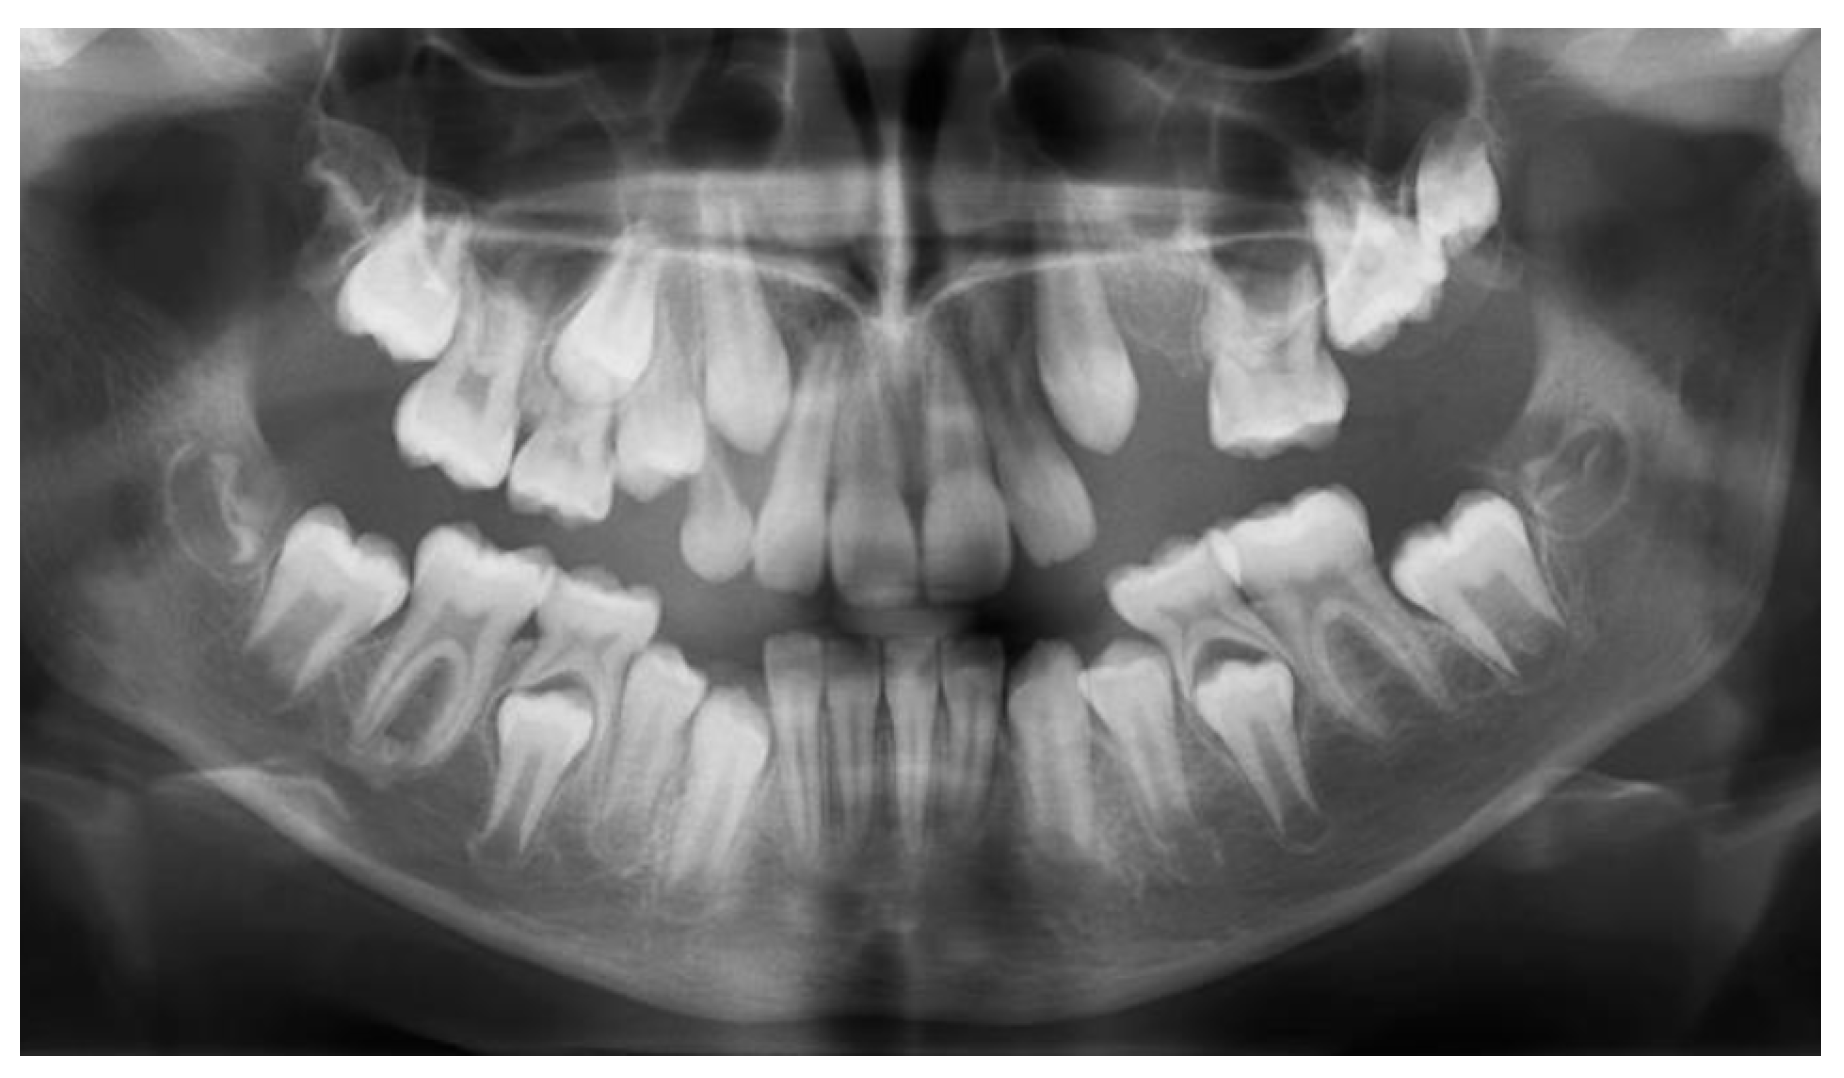

At the age of 7 y and 10 m, 65 had erupted, with an atypical crown shape and size (larger than usual, almost like a first permanent molar) (Figure 3a,b). Furthermore, no premolar buds could be seen in the upper left quadrant, and the unerupted 26 had reached the coronal stage, while 27 had a delayed development as compared to 17 (Figure 3c). Tooth 64 had become more intruded and seemed to be impacted by 63. PFE of the upper left permanent molars was suspected. Bimaxillary crowding and class II malocclusion were also noted. Caries prevention measures were applied, such as professional cleaning and glass-ionomer sealants on erupted first permanent molars (16, 36, and 46).

Figure 3.

Age of 7 y and 10 m. (a) Frontal view showing slight shift of the upper midline to the left and lower crowding; (b) occlusal view of both arches: 65 fully erupted, with atypical crown shape and size; (c) panoramic X-ray showing impacted 64, bimaxillary crowding, and a tendency for re-inclusion of 74.